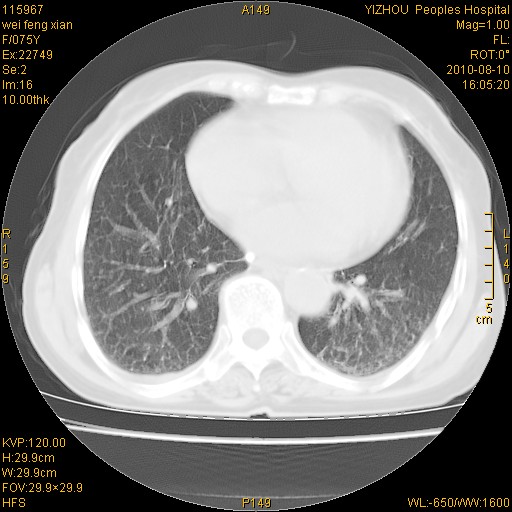

标题: CT28313:两肺弥漫性病变 [打印本页]

标题: CT28313:两肺弥漫性病变

女,75岁,患者反复头昏乏力面色苍白3年,再发10天入院。临床贫血查因。

双肺间质增生并右肺上叶炎性改变,不除外右肺上叶结核病肺内播散

考虑慢支伴右上肺慢性感染可能性大,建议结合临床排外尘肺可能。

考虑尘肺可能性大.

考虑右肺上叶炎症合并双肺结核可能性大,建议上传纵隔窗ct图片。

双肺结核可能性大

考虑尘肺并结核;右上肺支气管扩张!

结核、尘肺、支气管肺泡癌都不能除外

右肺上叶继发性肺结核伴肺内血型播散!

考虑右肺上叶继发性肺结核伴两肺播散。